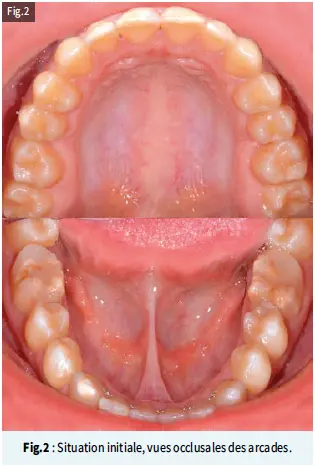

Les premières molaires mandibulaires de couleur brunâtre ont subi une dégradation post-éruptive, avec des restaurations en résine composite atypiques. On observe une asymétrie des défauts en ce qui concerne la localisation et le degré d’atteinte (Fig.2).